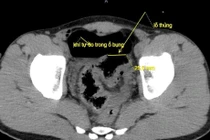

Dị vật là tăm tre trong bụng bệnh nhân/ Ảnh SKĐS